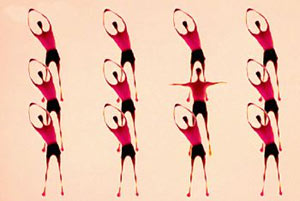

تسکین درد آرتروز زانو با تمرینات کششی

تمرینات کششی که باعث بهبود قدرت و توان عضلات اطراف زانوشده، از زانو ها حفاظت کرده و درد آرتروز زانوی شما را کم می کند. تمرینات کششی همچنین سفتی عضلات را بر طرف می کند و خطر به زمین افتادن را کاهش می دهد..